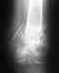

Возможно ли пройти у вас лечение, в связи с травмой.Заключение МРт:МР-признаки частичного повреждения ПКС и внутренней боковой связки. Краевой фокальный импрессионный перелом заднего края наружного мыщелка большой берцовой кости на протяжении 6 мм в глубину до 2,5 мм. дистрофические изменения медиального мениска. синовит. мне 40 лет. Гражданство РФ